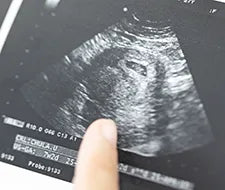

Wenn du in der 20. Woche schwanger bist, dann ist die Hälfte deiner Schwangerschaft bereits um. Du befindest dich jetzt im fünften Monat bzw. im zweiten Trimester. Dein Babybauch wird immer runder und die Entwicklung deines Babys schreitet weiter voran. Vor allem das Wachstum und die Gewichtsszunahme stehen im Fokus.

In unserem Schwangerschaftskalender fassen wir für dich zusammen, wie sich dein Baby in der SSW 20 entwickelt und wie es sich verändert. Du erfährst außerdem, wie sich die Größe und das Gewicht in dieser Schwangerschaftswoche erhöhen. Wir zeigen dir darüber hinaus, wie es dir geht, welche Symptome typisch sind und was bei der zweiten großen Vorsorgeuntersuchung auf dich zukommt.